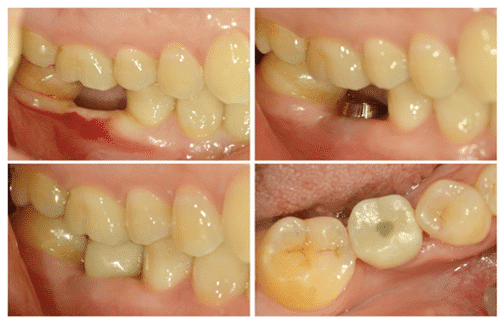

En effet, la hauteur de 2 mm du Magic Post joue un rôle crucial dans l’obtention d’une polyvalence dans la fabrication prothétique. Grâce à sa faible hauteur de 2 mm et à son angle externe incliné, il peut s’adapter à une variété de techniques prothétiques implantaires basées sur la dentisterie implantaire moderne (figures 16, 17).

(Figure 16) Forme spécifique du Magic Post.

(Figure 17) Traitement prothétique implantaire réussi, malgré une faible hauteur osseuse verticale.